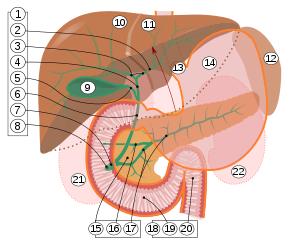

9. Gallenblase, 10–11. Linker und rechter Leberlappen. 12. Milz.

13. Speiseröhre. 14. Magen. 15. Bauchspeicheldrüse: 17. Ductus pancreaticus.

18. Dünndarm: 19. Zwölffingerdarm, 20. Jejunum

21–22: Nieren

Die menschliche Gallenblase ist normalerweise 8 bis 12 cm lang und 4 bis 5 cm breit. Ihre Form wird oft als „birnenförmig“ beschrieben. Die Gallenblase liegt in der Gallenblasengrube (Fossa vesicae biliaris) der Unterseite der Leber zwischen deren Lobus quadratum (quadratischer Lappen) und Lobus dexter (rechter Lappen) an, kann aber auch vom Gewebe der Leber umschlossen sein. Nach kaudal steht das Organ in Beziehung zur Flexura coli dextra, der rechten Biegung des Dickdarms (Colon), was bei Entzündungen zu Verwachsungen zwischen den beiden Organen führen kann, oder auch zu Verbindungen zwischen den jeweiligen Hohlräumen (biliodigestive Fistel). Dorsal (rückenwärts) befindet sich die Gallenblase nach medial in unmittelbarer Nähe der Pars superior des Zwölffingerdarms (Duodenum).[2] Bei den Schlangen liegt die Gallenblase hinter der Leber und relativ weit von dieser entfernt.

Das Organ kann in einen Fundus vesicae biliaris (Gallenblasenboden), Corpus vesicae biliaris (Gallenblasenkörper) und Collum vesicae biliaris (Gallenblasenhals) gegliedert werden.[2] Der Hals der Gallenblase, wo das Organ in den Ductus cysticus (Gallenblasengang) übergeht, besitzt eine spiralförmige Schleimhautfalte (Plica spiralis, auch Heister-Klappe), die eine Verschlussfunktion vor allem bei der Erhöhung des intraabdominalen Drucks z. B. beim Stuhlgang) wahrnimmt. Der Ductus cysticus vereint sich mit dem Ductus hepaticus communis zum Ductus choledochus, der im Ligamentum hepatoduodenale verläuft und in den Zwölffingerdarm mündet.[3]